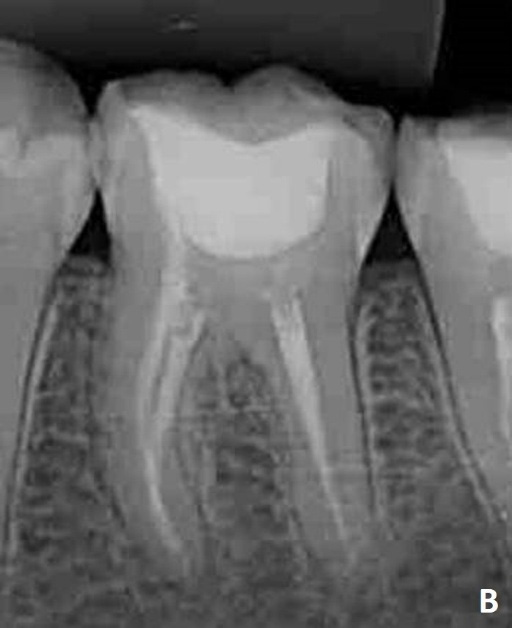

At the follow-up appointment, 1 year and 1 month after root canal filling, the patient reported no discomfort. Clinically, the resin restoration was well adapted, and radiographically there was no evidence of periapical lesion.

Final radiographic appearance